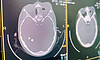

– При осмотре от пациентки исходил запах характерный для одонтогенного синусита. Это воспаление слизистой оболочки стенок верхнечелюстной пазухи, возникающее из-за распространения инфекционно-воспалительного процесса от больного зуба. Осмотрев полость рта, мы нашли кариозно-измененный и частично разрушенный зуб. Пациентке оперативно провели компьютерную томографию, на которой были выявлены гной в носу и в пазухе, разрушение нижней стенки орбиты. Сформировалась флегмона глазницы – воспаление орбитальной клетчатки с присутствием гнойного расплавления и некроза ее тканей, – рассказал врач-оториноларинголог Кировской областной детской клинической больницы Артем Катаев.

При данном заболевании за счет выраженного сдавления структуры глаза происходит отек зрительного нерва. И если он претерпит трофические изменения, то зрение потом будет либо очень плохое, либо вообще исчезнет. В данной ситуации необходимо было действовать быстро. В день поступления пациентке была проколота пазуха и установлен дренаж для промывания полости. Чтобы лечение имело эффект необходимо было устранить причину возникновения инфекционно-воспалительного процесса. На второй день врачами Кировского стоматологического центра был удален больной зуб, после чего к операции приступили врачи-оториноларингологи.